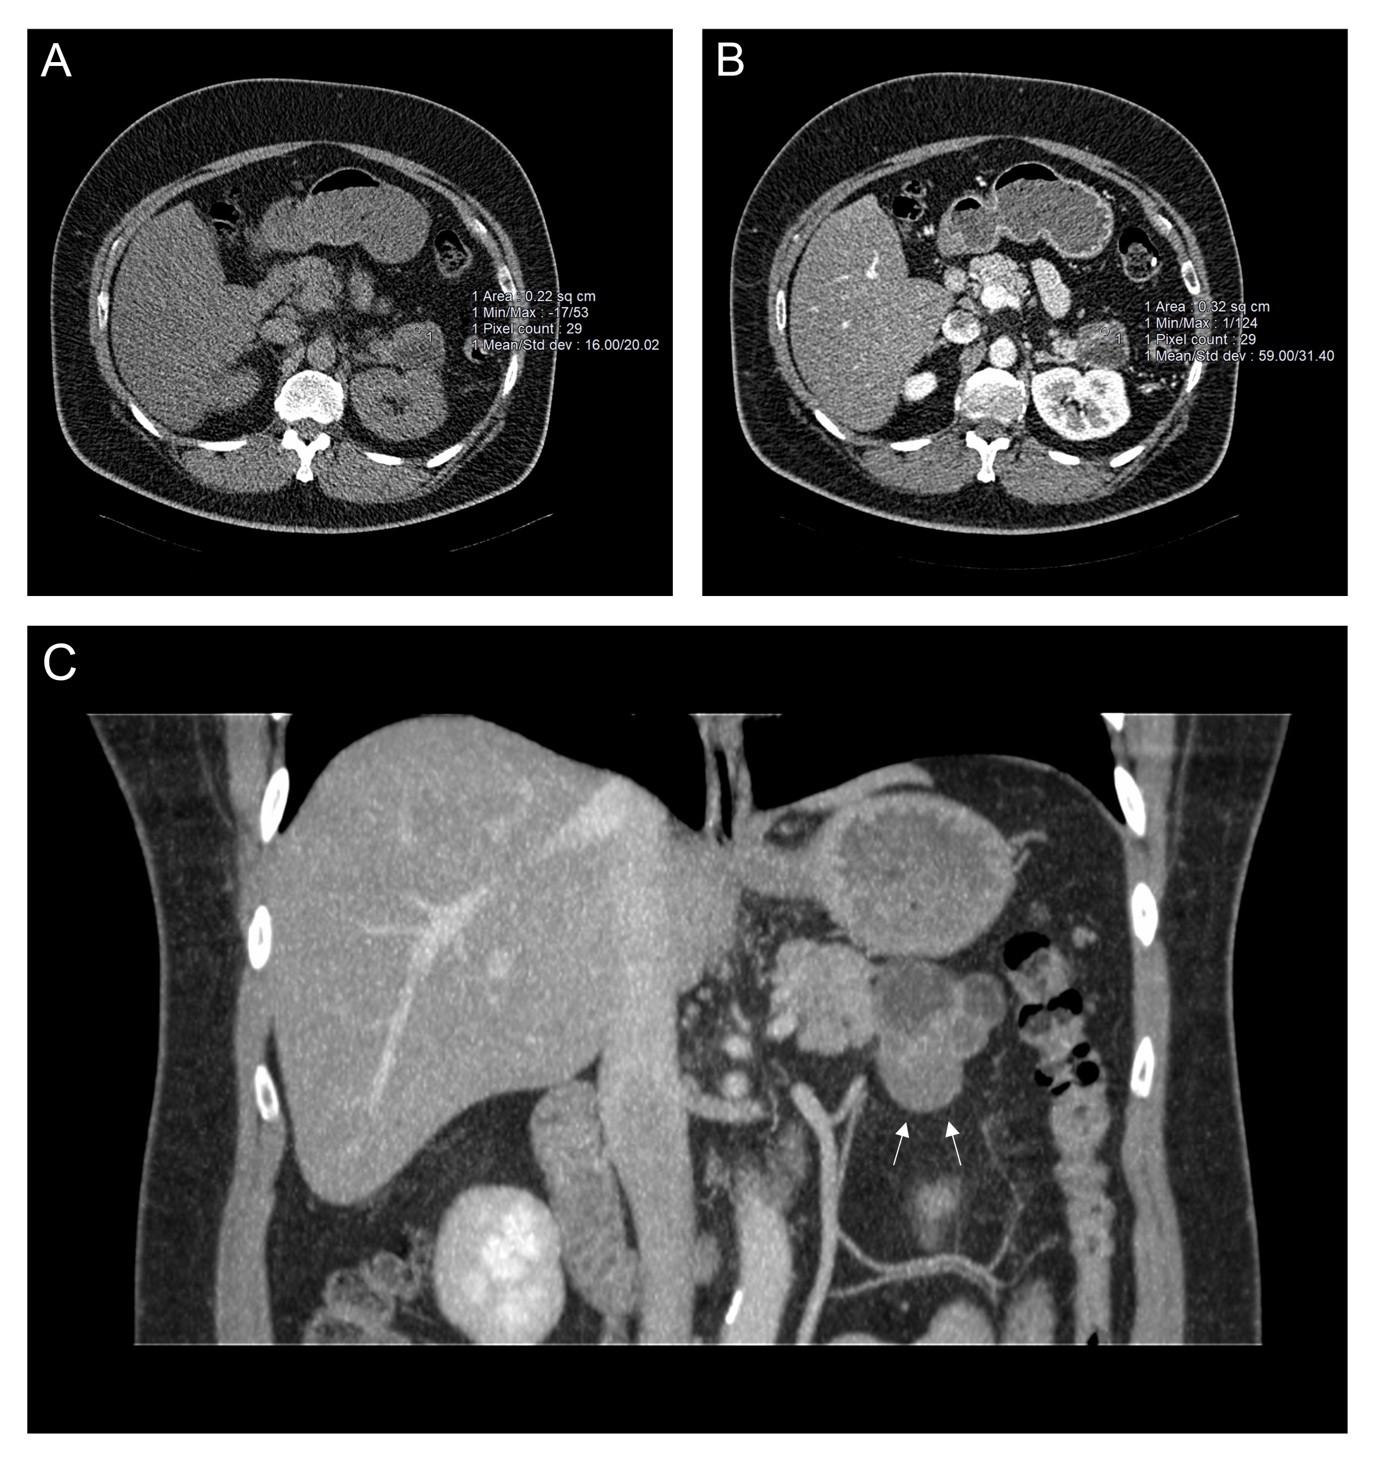

Pluvicto reduces progression of advanced prostate cancer